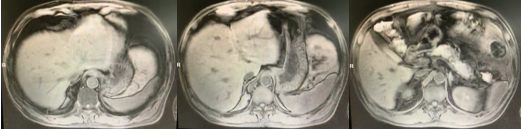

2019-6-18患者复查腹部增强CT:1.肝左叶病灶,转移?2.右输尿管上段病变,炎症?转移性病变?(图6)。2019-8-10复查腹部增强CT:1.肝左叶异常信号灶,请结合MRI增强?2.腹膜后多发小淋巴结,对比2019-6-18大致相仿(图7)。2019年8月16日上腹部MR增强:1.肝右叶S4段占位,倾向囊肿;2.肝左叶异常灌注考虑(图8)。

图8 患者复查上腹部增强MR影像资料(2019年8月16日)